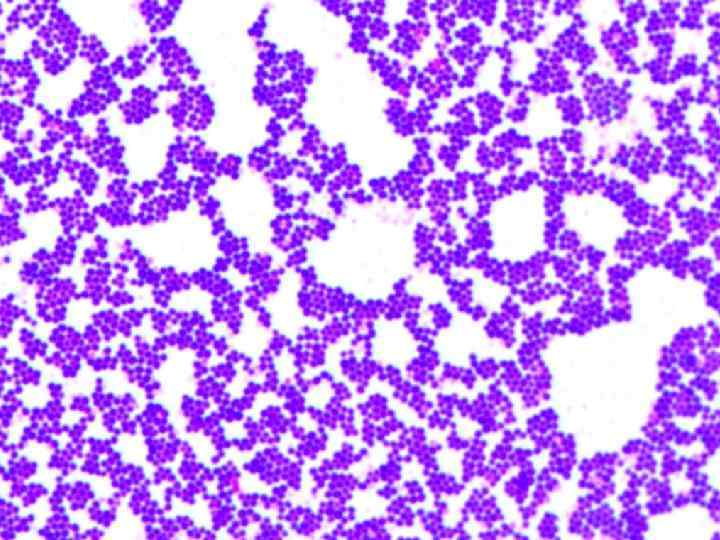

ЭТИОЛОГИЯ. Пищевые токсикоинфекции – собирательное название, объединяющее этиологически разные, но патогенетически и клинически сходные болезни. Заболевания могут вызываться различными условно-патогенными микроорганизмами свыше 30 разновидностей.

Чаще обнаруживаются возбудители ПТИ: Proteus vulgaris, Proteus mirabilis, споровыми аэробами (Bacillus cereus), споровыми анаэробами (Clostridium perfringens), Klebsiella, Enterobakter, Hafnia, Serratia, Pseudomonas, Aeromonas, Edwardsiella, В. citrobakter, гемофильными вибрионами (Vibrio parahaemalyticus), энтеротоксигенными штаммами стафилококков (St. aureus, St. albus), стрептококками (β гемолитический стрептококк группы А) и другие.